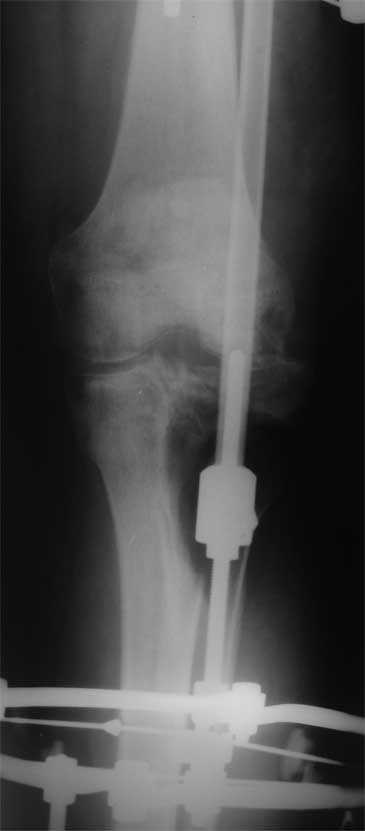

Я бы сделал пластику мягких тканей (торакодорзальный лоскут совместно с микрохирургами или пластику латеральной головкой икроножной мышцы) и выполнил бы краевой отщеп большеберцовой кости для его дистракции аппаратом в проксимальном направлении (рис. 1 – пример применения отщепа (авторство не мое), рис. 2 – схема предлагаемого варианта замещения дефекта кости).

2. Хотелось бы увидеть снимки раннего периода, лучше после травмы, а также КТ. Интересует целостность плато б/б кости. По представленным

снимкам возникает подозрение, что наружный мыщелок отделен. Или это так кажется?

> Хотелось бы увидеть снимки раннего периода, лучше после травмы, а также КТ. Интересует целостность плато б/б кости. По представленным

- нет, скорее всего не кажется, вероятно он отделен, но, скорее всего живой и неподвижный (иначе рассосался бы)